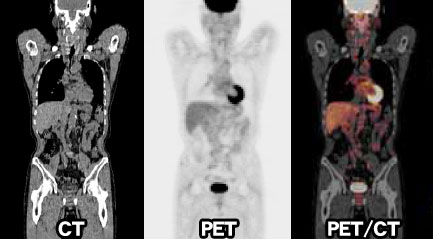

大腸がん肺転移時の治療法とは?~手術の条件や生存率について

大腸がんからの肺転移が起きたときの症状 肺は、呼吸で取り入れた酸素を全身に送る臓器です。肺の末梢にある肺胞には、酸素の運搬役をする血液が集まってきます。 そのた ...